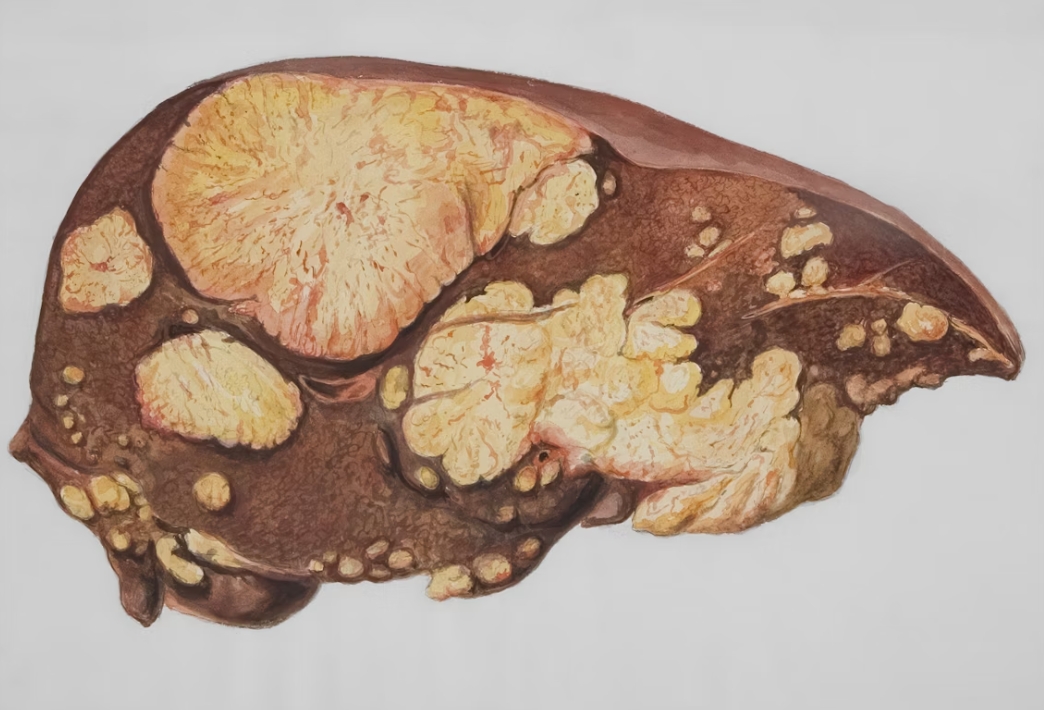

- B형·C형 간염

특히 ALT가 높다면 지방간이나 간세포 손상을, AST가 더 높다면 음주나 근육 손상 가능성을 함께 봐야 합니다.

간수치가 높다고 무조건 심각한 질환은 아니지만, 반복적으로 수치가 올라가거나 피로·소화불량·황달 같은 증상이 함께 나타난다면 반드시 원인을 찾아야 합니다. 특히 지방간, 간염, 음주, 약물, 수면 부족은 간수치를 높이는 주요 원인입니다. 건강검진 결과를 가볍게 넘기지 말고, 간이 보내는 신호를 조기에 확인하는 것이 중요합니다.